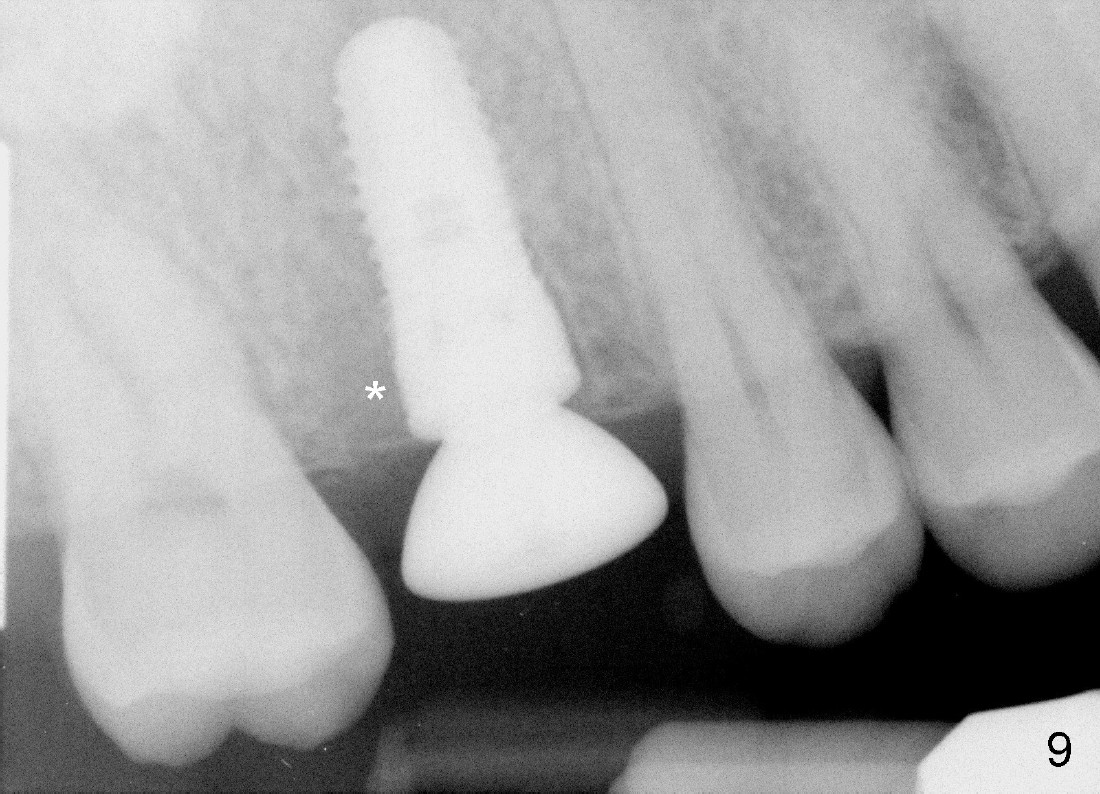

The tooth #3 has a crack line (Fig.1 ^). The septum (Fig.2 S) looks like an inverted pyramid (Fig.3), coronal part being pointed, whereas the apical broad. The shape of the septum is not so favorable to placement of tapered implant. Osteotomy starts with 1.5 mm pilot drill in the middle of the septum, followed by round tapered osteotomes 2 and 3 mm. The osteotomy begins to deviate into the mesiobuccal socket. The same osteotomes are used to re-direct the osteotomy palatally, followed by tapered drills, trying to move osteotomy palatally. A 4.5x17 mm tap is inserted with stability (Fig.4). Following using 5x17 mm tap at the depth of 12 mm, a 5.3x12 mm bone-level implant is placed ~ 1.5 mm below the crest, 1.5 mm above the septum (Fig.5). Demineralized cortical human allograft is placed in the remaining sockets and around the most coronal aspect of the implant (with a small piece of gauze placed in the implant well). After removal of the gauze, a piece of collagen membrane is pierced and carried by a 8.2x4/3 mm healing abutment and fixed in place (Fig.6 M). The periphery of the membrane is tucked underneath the gingiva. The wound is covered by perio dressing. The patient returns to clinic for follow up 8 days postop. There is no discomfort. In order to protect the collagen membrane (Fig.6), the perio dressing is intentionally not removed (Fig.7). Two weeks postop, the patient remains asymptomatic. After perio dressing removal, the membrane appears to have been resorbed (Fig.8 as compared to Fig.6). The bone graft (B), although exposed, remains in place and condensed, surrounded by healing healthy gingiva (*). The patient returns 2.5 months postop. The implant appears to osteointegrate (Fig.9, as compared to Fig.5). The buccal (Fig.10) and palatal (Fig.11) gingiva adapts to the healing abutment. When the healing abutment is removed for restoration 3 months postop, the gingiva looks healthy (Fig.12). A cemented abutment (5.8x4(2) mm) is placed; a crown is fabricated (Fig.13). The patient returns for recall 5 months post cementation. He reports food impaction distal to the crown. The gap mesial to the implant has closed (Fig.14).